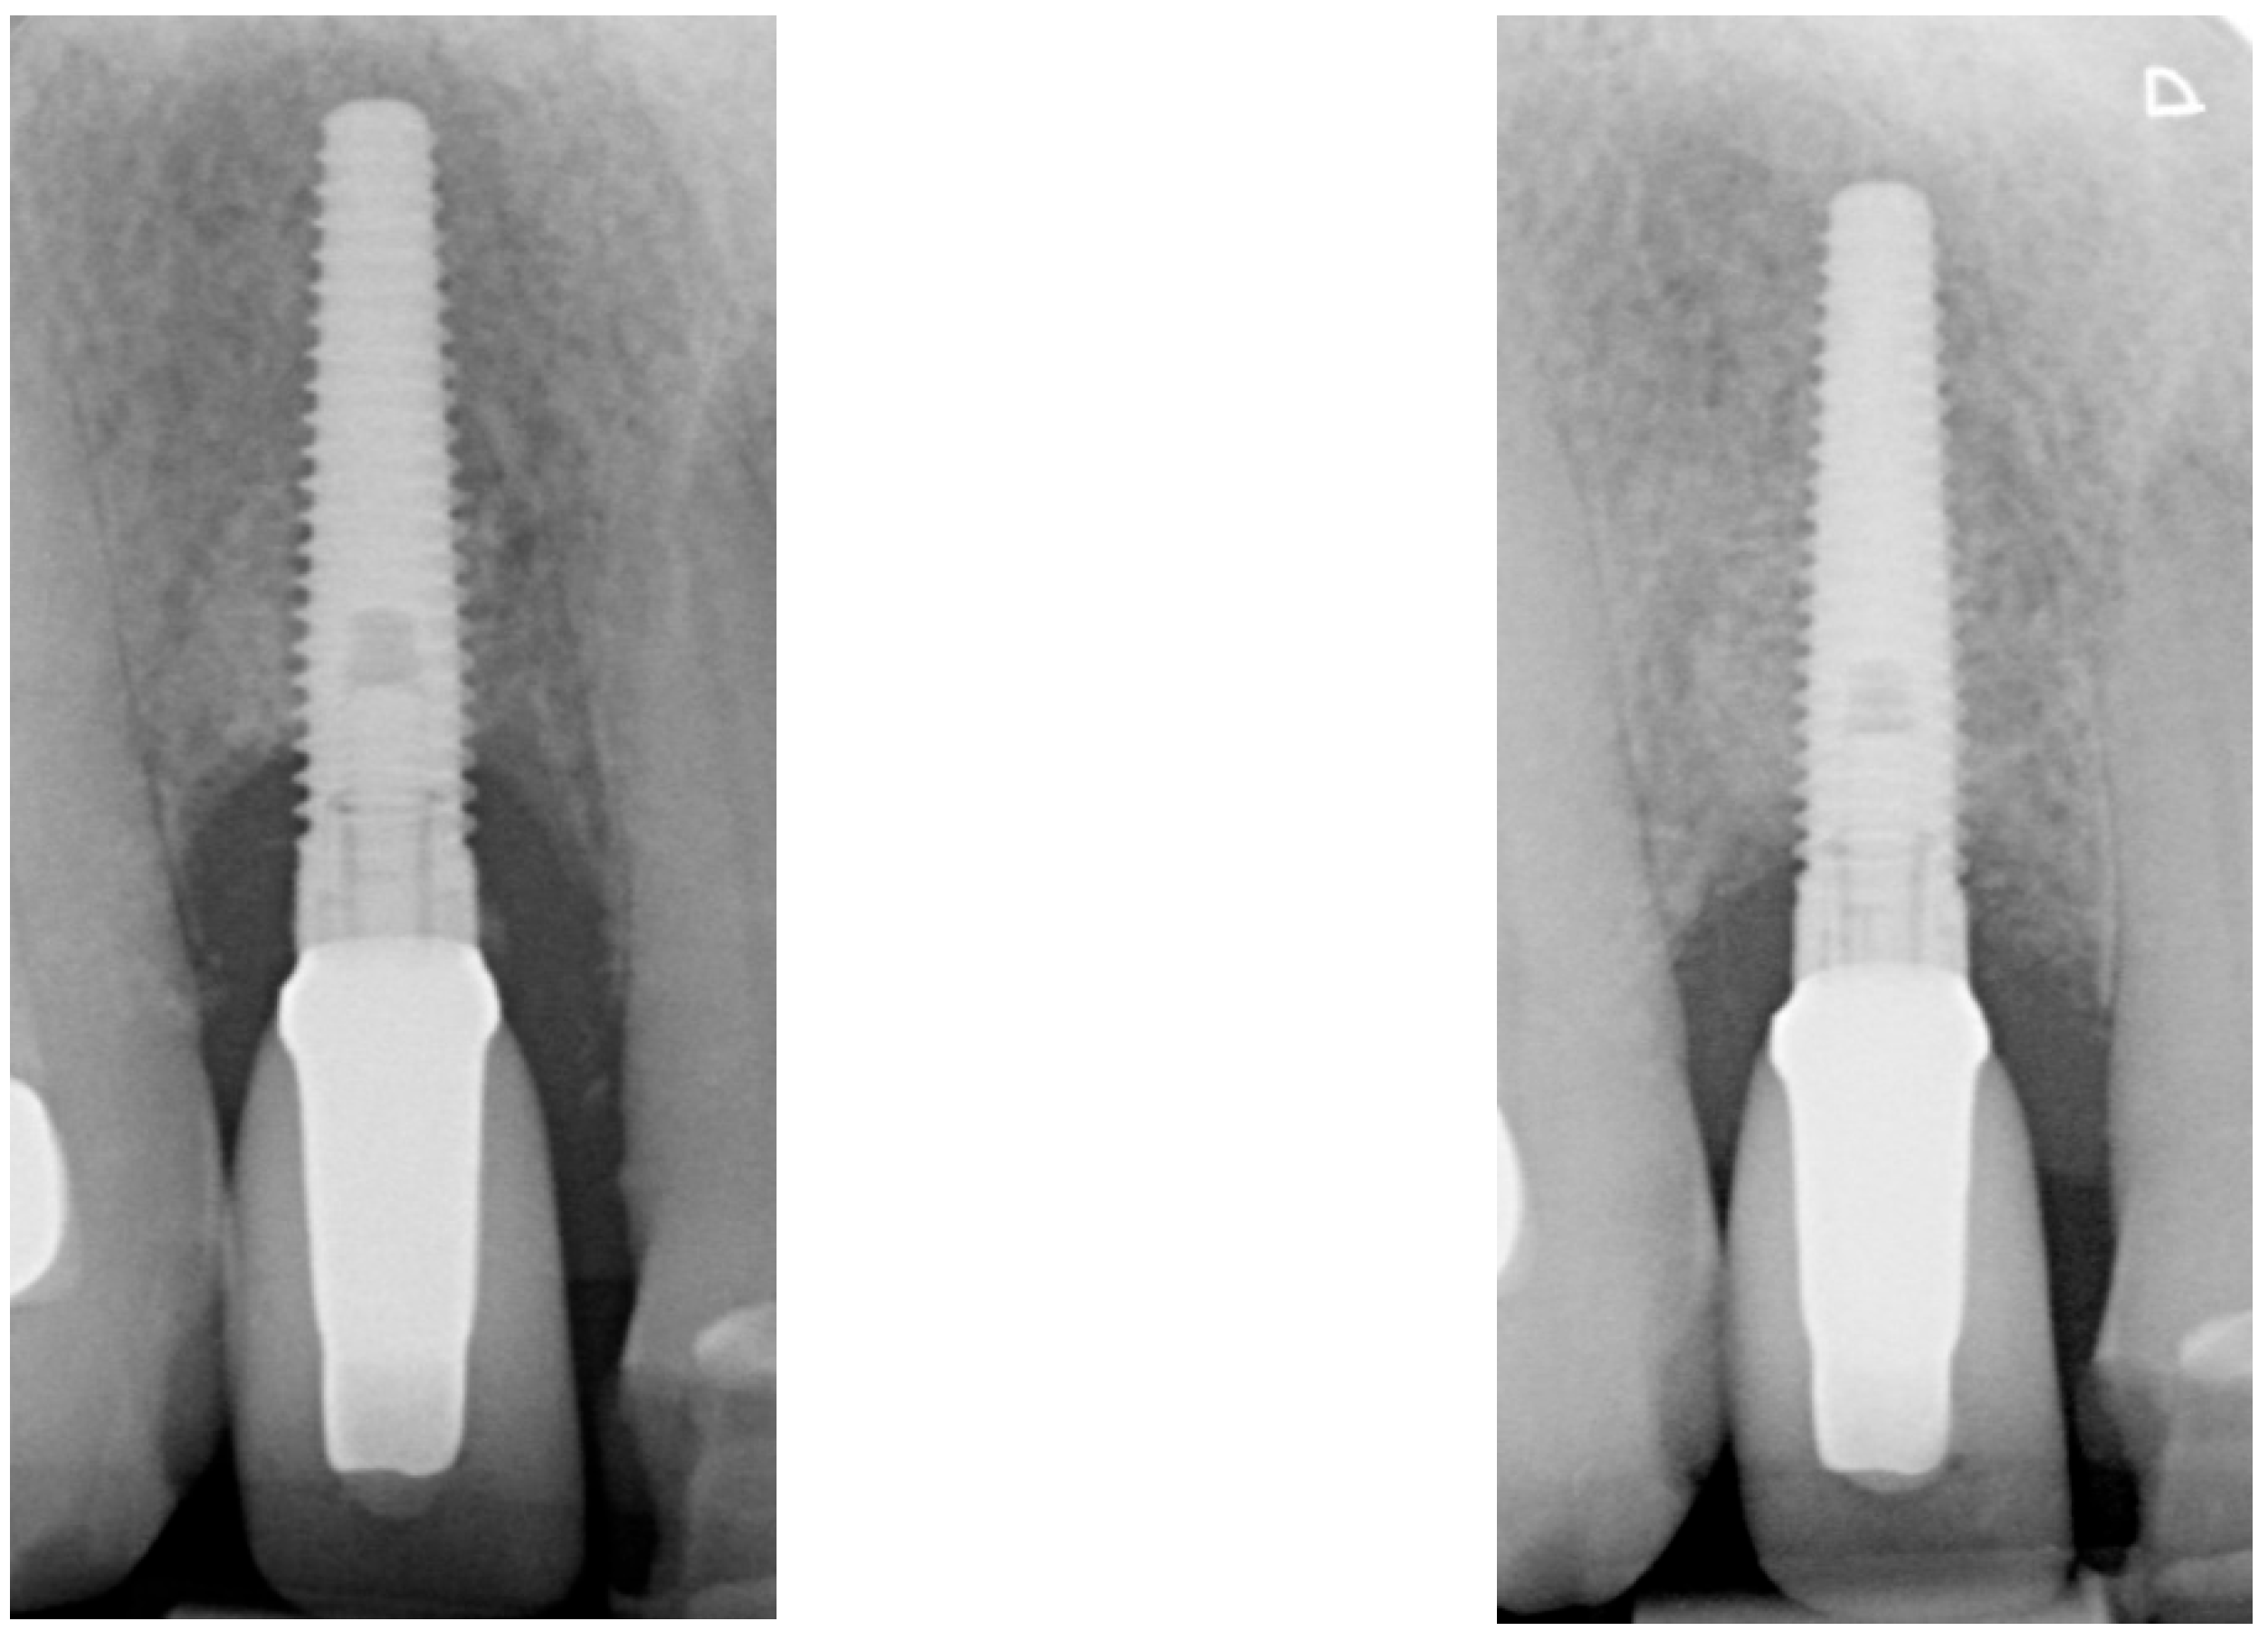

| Radiographic bone level at Tpre mesial (mm) | 5.6 | 3.8 | 1.7 |

| Radiographic bone level at Tpre distal (mm) | 7.6 | 4.2 | 3.2 |

| Radiographic bone level at T2 mesial (mm) | 0.4 | 3.5 | 0.0 |

| Radiographic bone level at T2 distal (mm) | 1.8 | 3.9 | 0.0 |

| Radiographic bone level at T6 mesial (mm) | 2.8 | 3.4 | 1.1 |

| Radiographic bone level at T6 distal (mm) | 3.5 | 0.7 | 2.5 |

| Radiographic bone level at T12 mesial (mm) | 2.3 | 2.5 | 1.7 |

| Radiographic bone level at T12 distal (mm) | 3.5 | 1.5 | 2.5 |